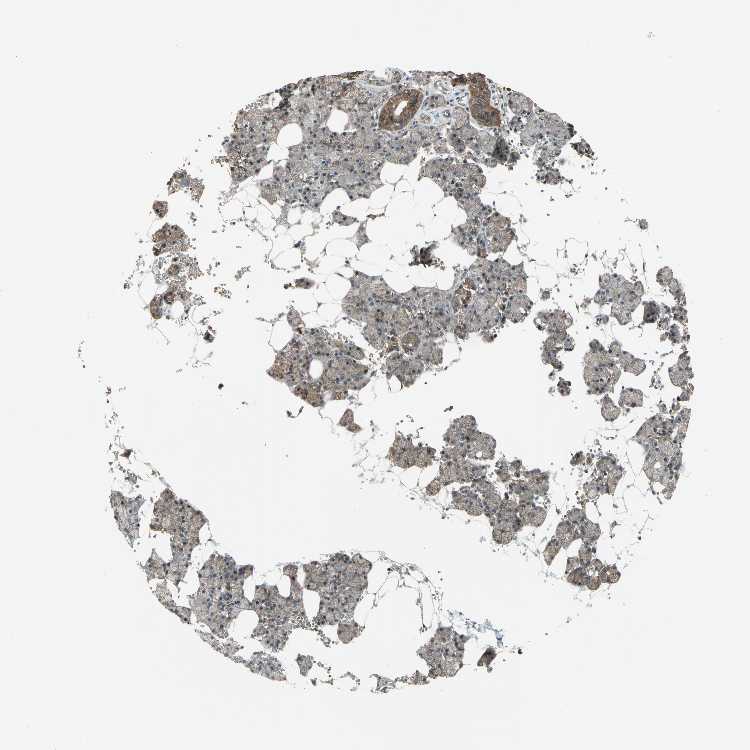

SALIVARY GLAND - Antibody stainingi

Antibody staining in the annotated cell types in the current human tissue is reported as not detected, low, medium, or high, based on conventional immunohistochemistry profiling in selected tissues. This score is based on the combination of the staining intensity and fraction of stained cells.

Each image is clickable and will lead to virtual microscopy that enables deeper exploration of all samples and also displays staining intensity scores, fraction scores and subcellular localization as well as patient and tissue information for each sample.

Antibody CAB010261

Glandular cells Medium